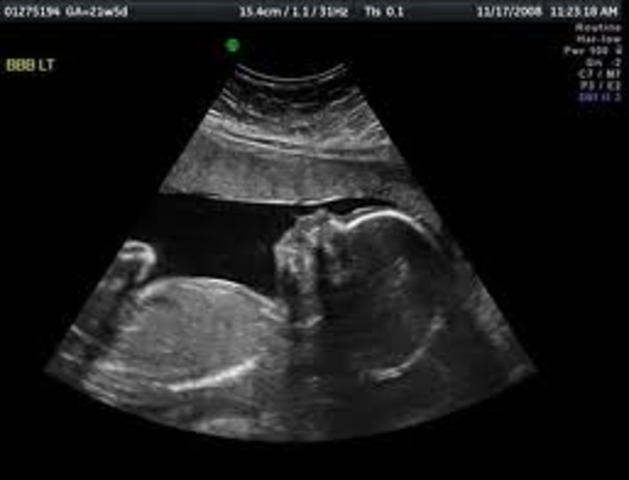

• Month 5- Baby

Month 5- Baby

The size of the baby is about 6 1/2 -7 in. (16-18cm) long. About 4-5 oz. (113-142g). Hair, eyelashes, and eyebrow's appear. Teeth continue to develope. Organs are maturing. Becomes more active.